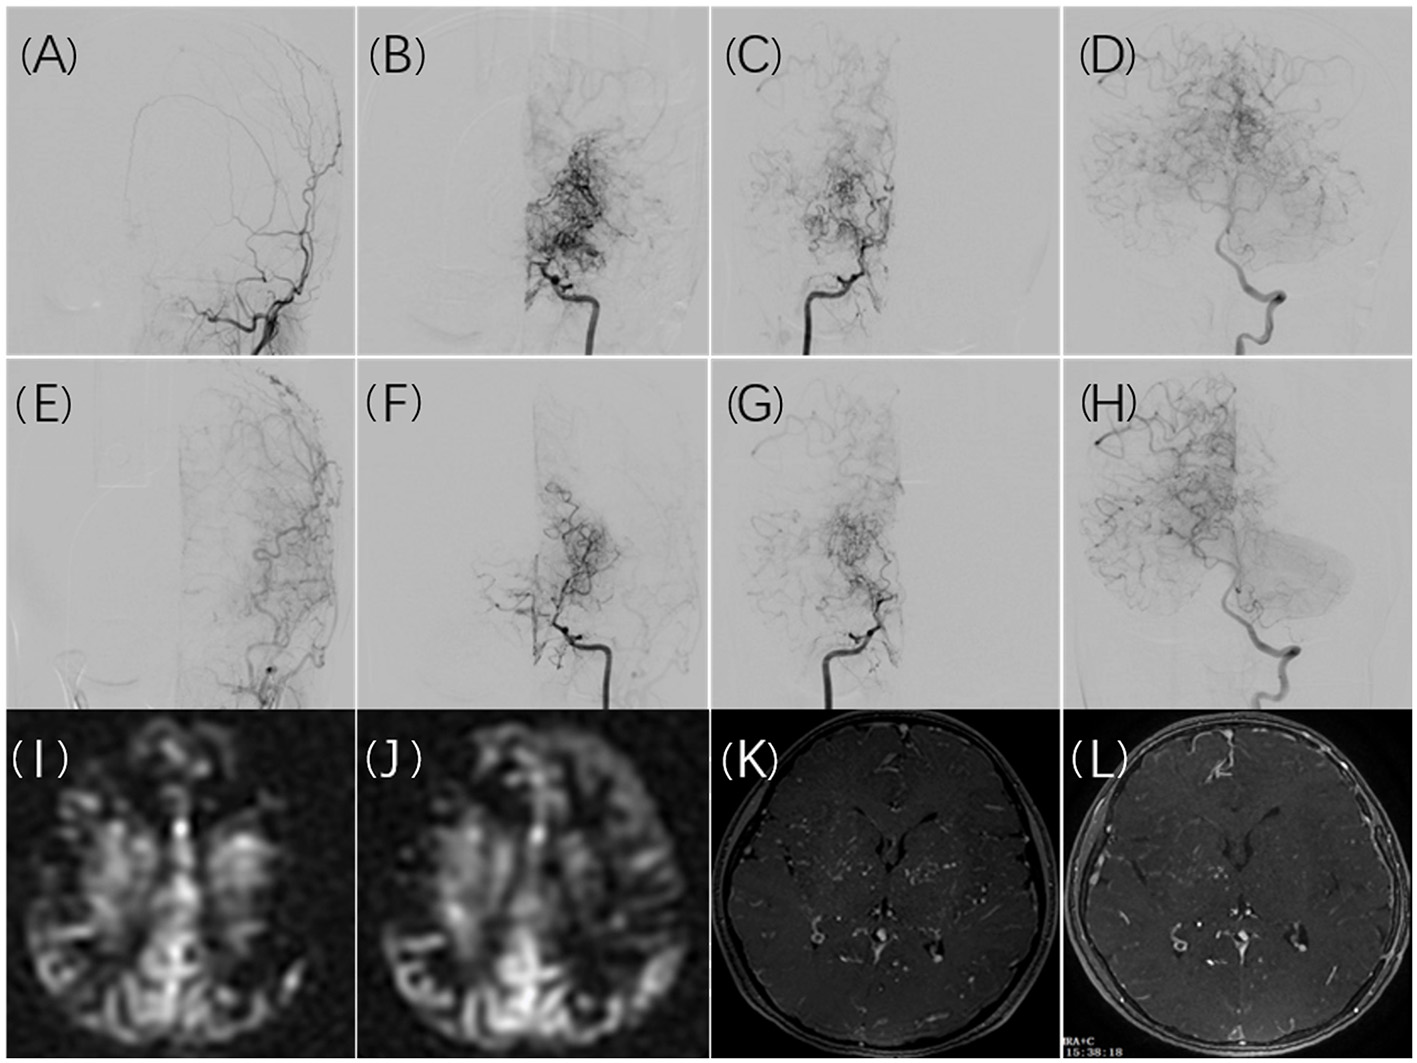

A significant difference was observed between the incidence of cerebral infarction following the first revascularization and the incidence following the second revascularization. This may be partly because the first surgery is more likely to be performed in the symptomatic hemisphere. However, some findings in the literature as well as our study led us to conclude that the first revascularization procedure improves cerebral blood flow reserve, which allows patients to better tolerate hemodynamic instability in the second operation. After the first surgery, 16 (39%) of the 41 infarct events occurred at contralateral hemispheres. However, there were no infarct events in the contralateral hemisphere after the second surgery. According to imaging examinations performed before the second revascularization surgery, cerebral blood flow and cerebral perfusion had improved to varying degrees in most postoperative hemispheres, and bilateral improvement had been noted in some patients. As reported in a study published in 2021 (26), cerebral reactivity and TIA frequency in the contralateral hemisphere can be improved following unilateral revascularization surgery in bilateral MMD. Figure 2 illustrates the imaging changes observed in patients with bilateral MMD after unilateral surgery in a typical case. Revascularization significantly improved blood supply to the postoperative hemisphere, resulting in a redistribution of blood flow, the cerebral vascular supply range shifting from the postoperative hemisphere to the un-operated hemisphere, and a uniform cerebral perfusion pattern. The dilated and disordered vascular morphology of the bilateral cerebral hemispheres was also partially restored.

Figure 2

A 10-year-old girl presented with recurrent numbness of the right limbs. Cerebral angiography revealed bilateral moyamoya disease (B,C) without collateral anastomosis for the left ECA (A). Collateral compensation from the posterior circulation was noted (D). Six months after surgical revascularization, the left ECA angiogram demonstrated graft patency and good angiogenesis (E). Shrinkage of moyamoya vessels on both hemispheres was noted (F,G), and the left internal carotid artery compensated for the right hemisphere (F). The compensatory range of the posterior circulation shifted to the non-operated territory (H). The MRI ASL images showed hypoperfusion in the cerebral cortex (I). The hypoperfusion in the left cortex improved after surgical revascularization with a decrease in perfusion in the left basal ganglia (J). Ivy collateral vessels in contrast MRA decreased obviously in the left and right basal ganglia after surgical revascularization (K,L).